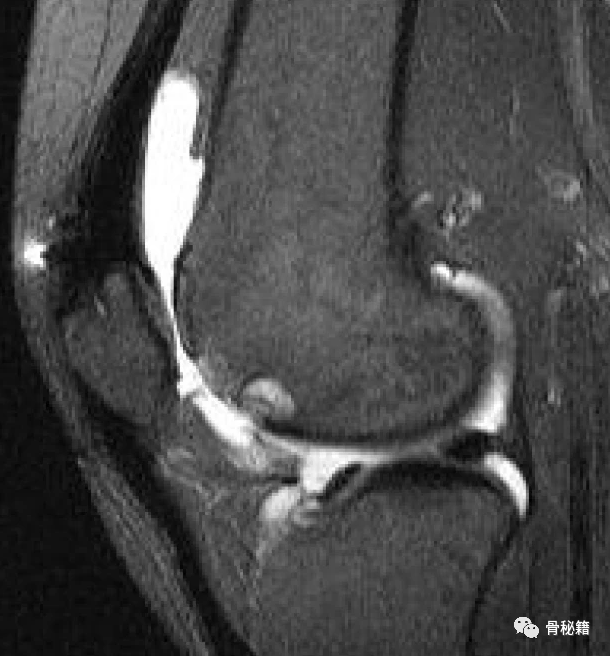

PFOA 有 4 种类型。最常见的类型是基于外侧的 PFOA,它与髌股关节发育不良有关,有或没有外侧髌骨不稳定的病史。基于内侧的 PFOA 与膝内翻或先前的髌骨稳定外科手术相关,例如内侧胫骨结节截骨术或外侧松解术。PFOA 与原发性骨关节炎 (OA) 相关,但也与创伤后 OA 或类风湿性关节炎等全身性疾病相关。中央滑车 OA 与具有高屈曲要求(例如跪姿和跳跃活动)的患者相关。